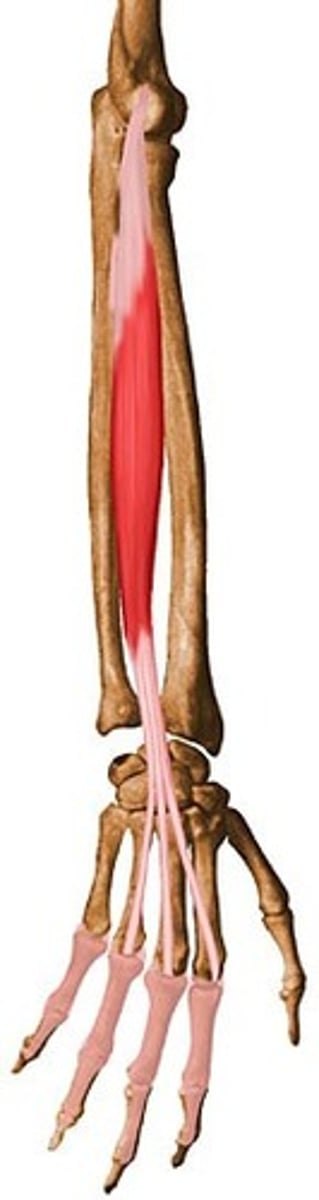

Extensor digitorum m.

A

Extends digits 2 - 5

Extends wrist

Inn

Radial n.